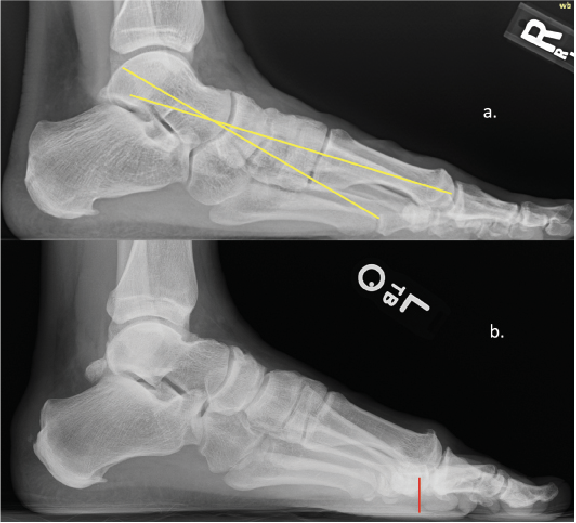

Either way, the multiple classification systems available should not be utilized alone to determine surgical treatment. More often I find that these systems ignore instability, elevation, or metatarsal length. As some studies concluded, classification failed to correlate with every patient.7,8 Roukis and colleagues in 2002 presented his four-stage radiographic analysis—which finally incorporated some radiographic measurements to include metatarsal protrusion, intermetatarsal angle, and talo-first metatarsal angles—which looks at elevatus, as shown in Figure 2 above and Figure 3 below.9 He then followed that up with an article on metatarsus primus elevatus in 2005.10 Then Elliott and colleagues’ 2016 follow-up review11 on Roukis’s 2002 study9 concluded that regardless of the etiology or surgery performed, patients were happier; however, their ROM never improved.

long history of plantar fasciitis. B. The below X-ray shows elevation, with the first metatarsal head not even touching the floor.